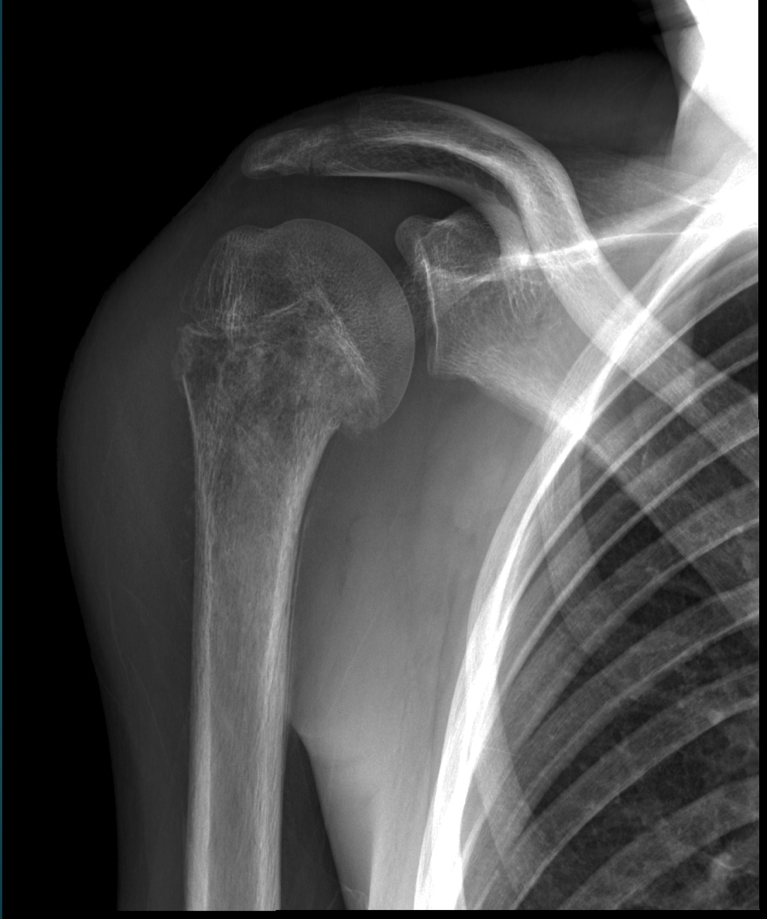

15 YO M. Arm pain and swelling

A 15 YO male patient presents with swelling at the R. arm, fever, radiographic findings show laminated periosteal response in the diaphyseal location. Which TWO possible diagnosis will you consider?

B. Ewing’s sarcoma

D. osteomyelitis